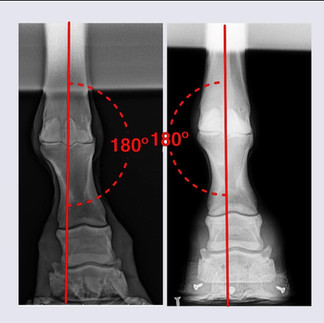

1) Collage 1

Right fore

Left-pre 1st shoeing -7/22 rad

Right- post 6th shoeing -7/23 rad

A year’s timeline on a founder case, we have lowered the PA 7 degrees to date, restored sole depth and are decreasing the lamellar wedge and restoring more functional proportions.

The added change has been a more axial balance to the fores; from a substantial carpus valgus presentation to considerably closer to what’s appropriate.

Image 8 - proofs in the radiographs, Abby’s one happy young mare. Written off as a rotational founder w/ no future, her future is improving with every passing month as her feet remodel and rebuild, changing her conformation, posture, hoof balance and proportions.